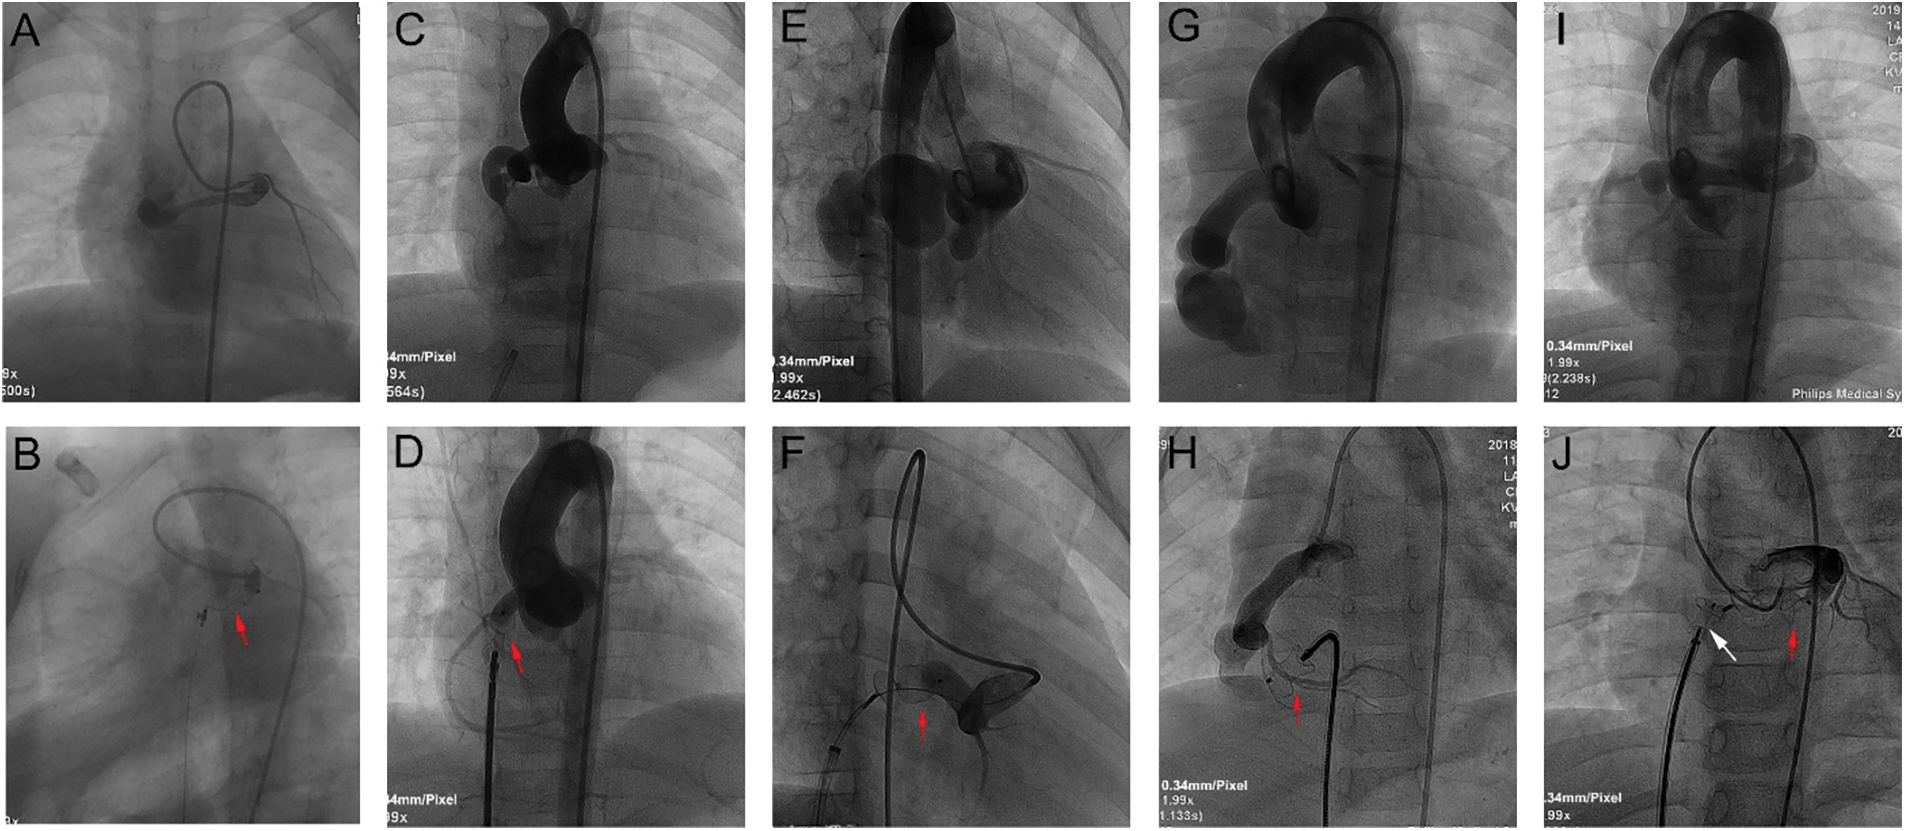

Details of TCC are summarized in Table 3. During procedure, antegrade venous/arterial or retrograde arterial approach after the A-V/A-A loops was used in 53 cases (80.3%), and retrograde arterial approach was used in 13 cases (19.7%, Fig. 3). The CCFs were occluded at the proximal site in 22 patients (33.33%), at the distal site in 42 patients (63.64%), and at both sites in 2 patients (3.03%, Fig. 4). Types of devices used in the closure procedure are presented in Table 3. PDA occluder was most commonly used (27.3%), followed by AVP II (22.7%), and VSD occluder (mainly muscular VSD occluder) (16.7%).

Figure 4: TCC of CCFs with different occlusion sites. A, B: Selective left coronary angiogram in anterior and caudal LAO projections demonstrated an LCA-to-RA fistula. A 10 mm AVP (red arrow) was deployed at the proximal site near the fistula origin. C, D: Ascending aortogram in anterior projection demonstrated an RCA-to-RA fistula. A 6/8 mm PDA occluder (red arrow) was deployed at the fistula orifice (distal site). E, F: Ascending aortogram in RAO 30° projection demonstrated an RCA-to-RA fistula with a giant CAA. A 12 mm domestic vascular plug (red arrow) was deployed at the proximal site near the CAA inlet. G, H: Ascending aortogram in anterior projection demonstrated an RCA-to-RV fistula with a giant CAA. A 10/12 mm PDA occluder (red arrow) was deployed at the distal site near the CAA outlet. I, J: Ascending aortogram in anterior projection demonstrated an LCA-to-RV fistula. A 10/12 mm PDA occluder (white arrow) was deployed at the distal site near the CAA outlet, and a 12 mm domestic vascular plug (red arrow) was deployed at the proximal site near the CAA inlet

Notes: TCC: transcatheter closure; CCF: coronary cameral fistula; LAO: right anterior oblique; LCA: left coronary artery; RA: right atrium; AVP: Amplatzer vascular plug. RCA: right coronary artery; PDA: patent ductus arteriosus; CAA: coronary artery aneurysm; RV: right ventricle.